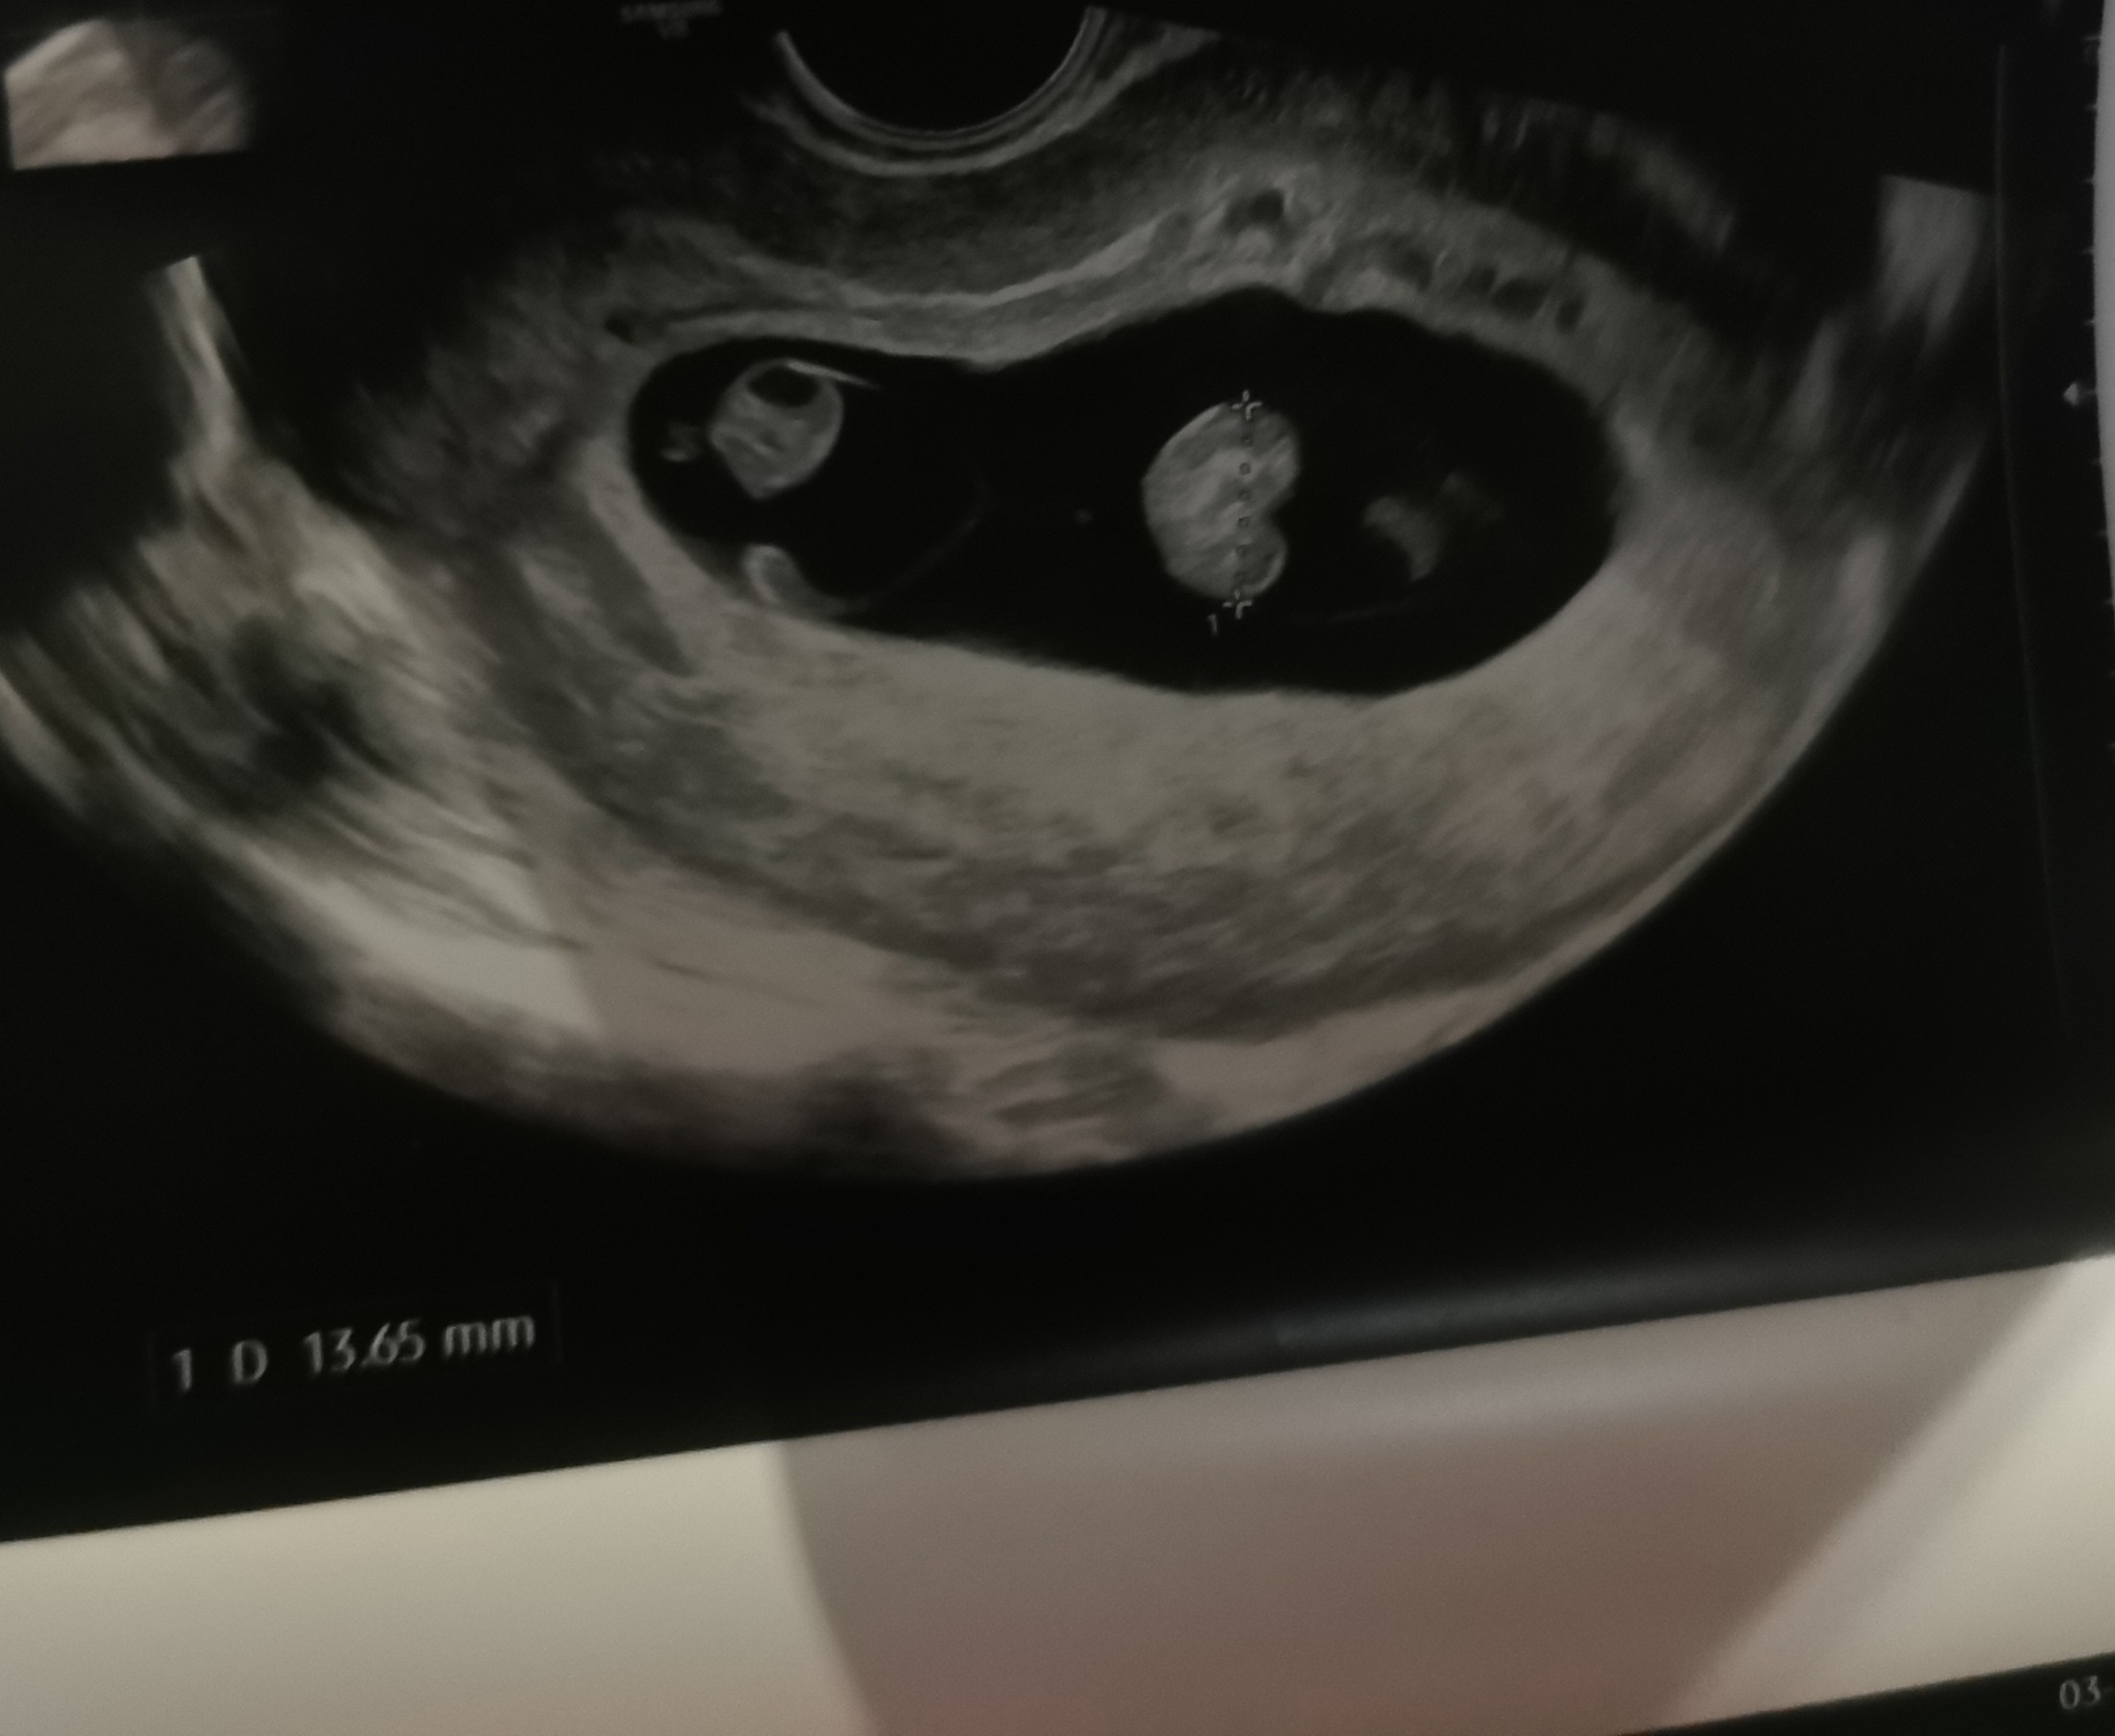

O matko, wszystko dobrze ...tylko Pan Doktor nas poinformował, że mamy 2 serduszka 😱. Będą bliźniaki. Tego się kompletnie nie spodziewaliśmy ... Jeszcze chyba nie oswoiłam się z tą myślą ....za 2 tygodnie muszę umówić wizytę bo nie wiadomo czy każdy bobas ma swoje łożysko, czy mają jedno wspólne ... trochę się denerwuję ... ale też cieszę ... jakoś to bedzie😊❤️❤️

U mnie to wygląda całkiem inaczej. Są dwa osobne te czarne pola z zarodkiem w środku . A u Ciebie dwa zarodki są w jednym worku, ale mogą mieć 2 łożyska ale być w jednej owodni. Tak to się nazywa chyba :) Tak czy tak szok. Ja też byłam w szoku i do tej pory jestem a wiem już z 3 tygodnie.